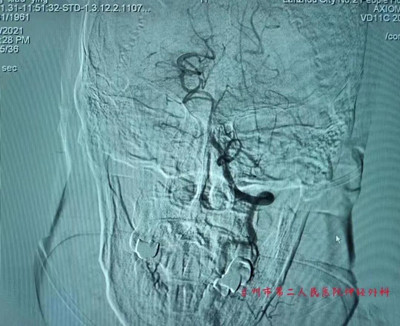

术前堵塞的基底动脉